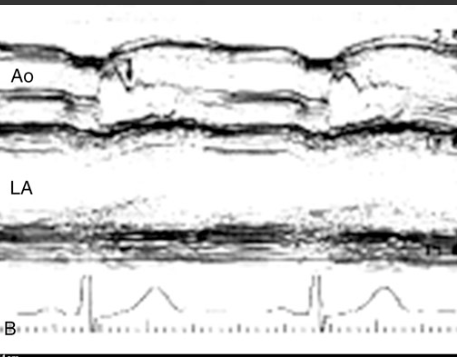

Mid systolic closure of aortic valve

Stress CM (Takotsubo)

What condition is seen in this 2D image?

What condition is it seen in?

Mid-systolic closure of aortic valve

HOCM